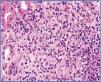

En la analítica se objetiva: leucocitosis con importante eosinofilia y fracaso renal agudo con creatinina: 6,1 mg/dl, urea: 156 mg/dl y niveles de vancomicina en 36,19 µg/ml (niveles normales: 5-10 µg/ml). Se suspende la vancomicina y se canaliza vía femoral derecha y realización de sesión de hemodiálisis. El estudio inmunológico, incluyendo anticuerpos antinucleares, anticuerpos anticitoplasma de neutrófilos, anticuerpos antimembrana basal glomerular y proteinograma, fueron todos normales. Se extraen hemocultivos y urocultivo, ambos estériles. Se extrae serología para virus de la hepatitis B y C, virus de la inmunodeficiencia humana, herpes virus, herpes 6, virus de Epstein-Barr, Chlamidia y Mycoplasma, todas negativas. Se instaura tratamiento con corticoides, 3 dosis diarias de 250 mg de metilprednisona, seguido de prednisona intravenosa a dosis de 1 mg/kg de peso, ante la sospecha inmunoalérgica del fracaso renal agudo. Posteriormente, cuando el estado general de la paciente lo permite, se decide la realización de biopsia renal. La biopsia renal incluye incluye 18 glomérulos, 6 de ellos con esclerosis global del ovillo capilar. En los 12 glomérulos conservados, no hay lesiones intracapilares significativas. Se observa una lesión tubulointersticial difusa de intensidad moderada con infiltrados inflamatorios polimorfos, formados por linfocitos pequeños, células plasmáticas y abundantes eosinófilos (figura 1) y numerosas imágenes de tubulitis con infiltrados de linfocitos a nivel del epitelio tubular. En las pequeñas arterias y en las pequeñas arterias intralobulillares no hay lesiones. Todo ello es compatible con el diagnóstico de nefritis tubulointersticial aguda con eosinófilos sugestiva de nefritis inmunoalérgica.

Figura 1. Tinción con hematoxilia-eosina